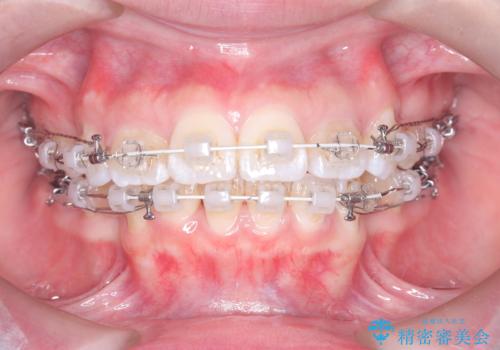

突き出た前歯を下げて理想的な横顔に。上下左右4番抜歯による審美ワイヤー矯正

精密検査の結果、歯を後方へ下げるためのスペースが不足していたため、上下左右の4番目の歯(第一小臼歯)を計4本抜歯する計画を立案しました。抜歯によってできたスペースを最大限に活用し、前歯を後ろに下げることで、口元のボリュームを抑え、バランスの良いEライン(横顔のライン)を目指すこととしました。装置は、日常生活で目立ちにくい審美ワイヤーを選択しました。

治療は、審美ワイヤーを用いて抜歯スペースを徐々に閉じながら、前歯の角度と位置を精密にコントロールして進められました。ワイヤー矯正は歯を三次元的にしっかりと動かすことができるため、前歯を単に倒すのではなく、根元から理想的な位置へと誘導しました。

1年半の治療期間を経て、抜歯したスペースは完全に閉じ、突き出ていた前歯はすっきりと内側に収まりました。噛み合わせの精度も向上し、機能面でも良好な結果が得られています。